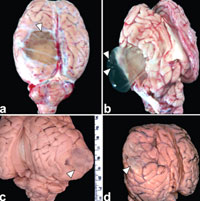

Về mặt hình thái học, các hình ảnh về nang sán nhiều đầu, một số nang được phẩu thuật loại bỏ khỏi bệnh nhân và một số khác phát hiện sau khi giải phẩu tử thi động vật chết.

Các nang sán có thể hiện diện trong cơ thể người bất kỳ nơi nào trong một vài tháng đến vài năm sau khi ăn phải. Một khi nang phát triển, các triệu chứng liên quan đến nang phát triển nhanh chóng. Trên người, nhiễm sán này gây ra một loạt các triệu chứng, lệ thuộc vào nơi nào mà nang sán ký sinh. Nhóm sán dây này cũng hình thành nên các nang chứa đầy dịch và nằm trong các vị khác mô khác nhau trong cơ thể. Các nang này ban đầu nhỏ, sau đó phát triển ấu trùng lớn dần và nang có thể đạt đến kích cỡ 1 quả trứng. Nang sán T. multiceps thường có đường kính khoảng 2 - 6 cm và hầu như tìm thấy trong hệ thần kinh trung ương và có thể chứa ở bất cứ nơi nào từ một vài đến vài trăm ấu trùng sán nằm bên trong chúng. Các nang sán loài T. serialis và T. glomerata hiện diện trong thàn kinh trung ương, cơ và mô dưới da, nang của loài T. brauni có thể chiếm nằm ở những vị trí giống nhau nhưng xảy ra trong mắt thường gặp hơn các vị trí khác so với 3 loài.